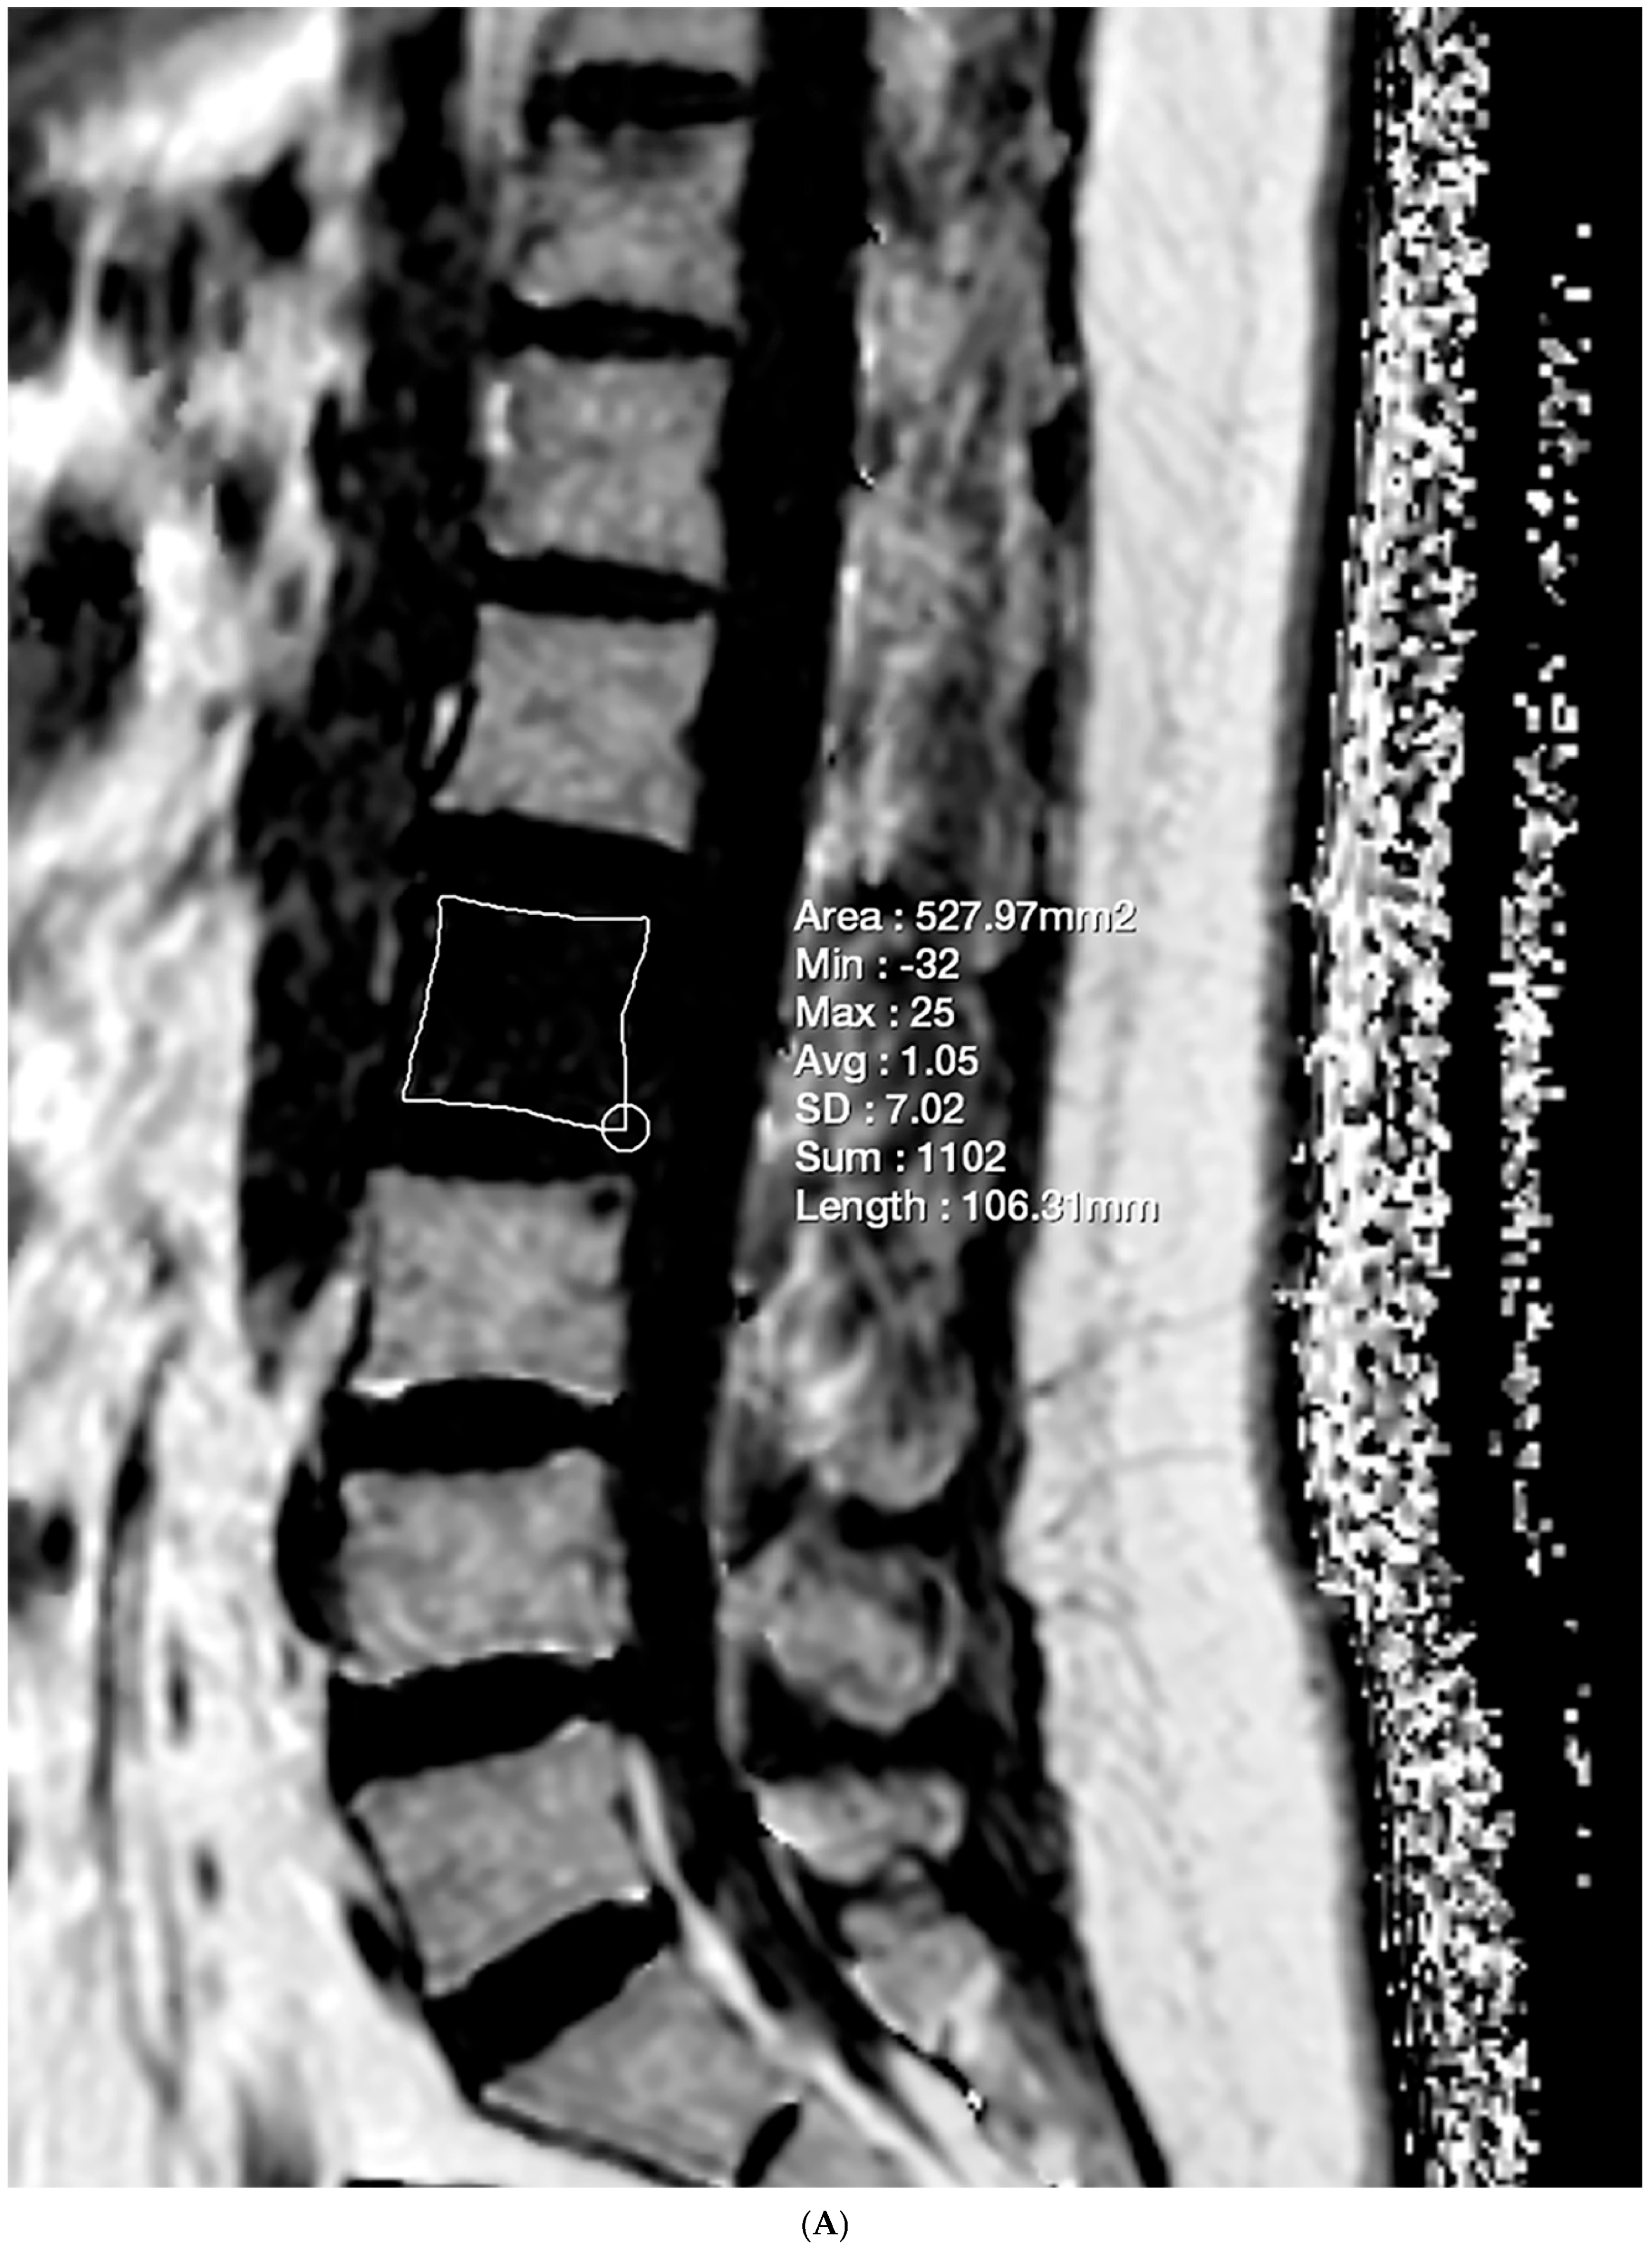

2.4. Vertebral Bone Quality Score Measurement